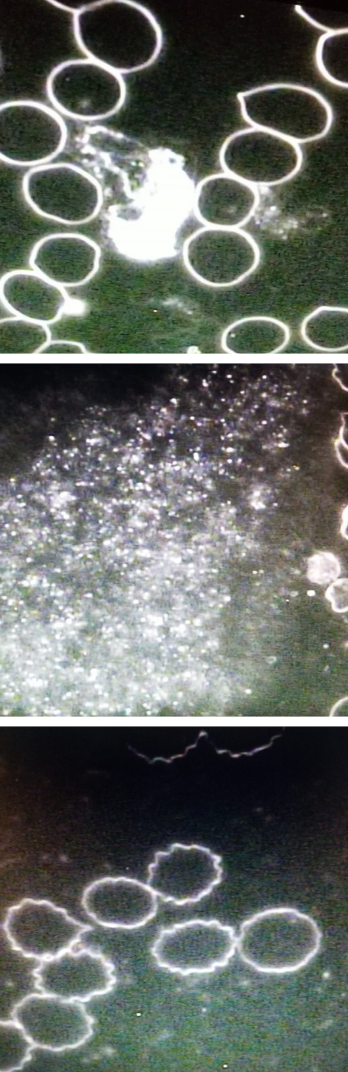

Live blood cell microscopy is a way to observe live blood cells (RBCs and WBCs) and the terrain within the blood (plasma and platelets). RBCs carry primarily oxygen and WBCs indicate that the body is fighting infection or disease (they are the "good guys" that are part of your immune system).

Live blood cell analysis involves taking a single “alive” drop of blood to observe it under a microscope at 1,000 times the size. The client and practitioner, together, can observe what is happening at a microscopic level and work towards improving nutritional intake and eliminating toxins through the emunctories. As protocols are put in place and adhered to, over time, we can also observe how improved nutrition affects the blood.